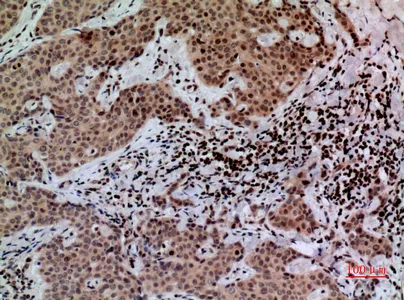

MPO Rabbit Polyclonal Antibody

Cat: APRab14056

Size1:50μl Price1:$118

Size2:100μl Price2:$220

Size3:500μl Price3:$980